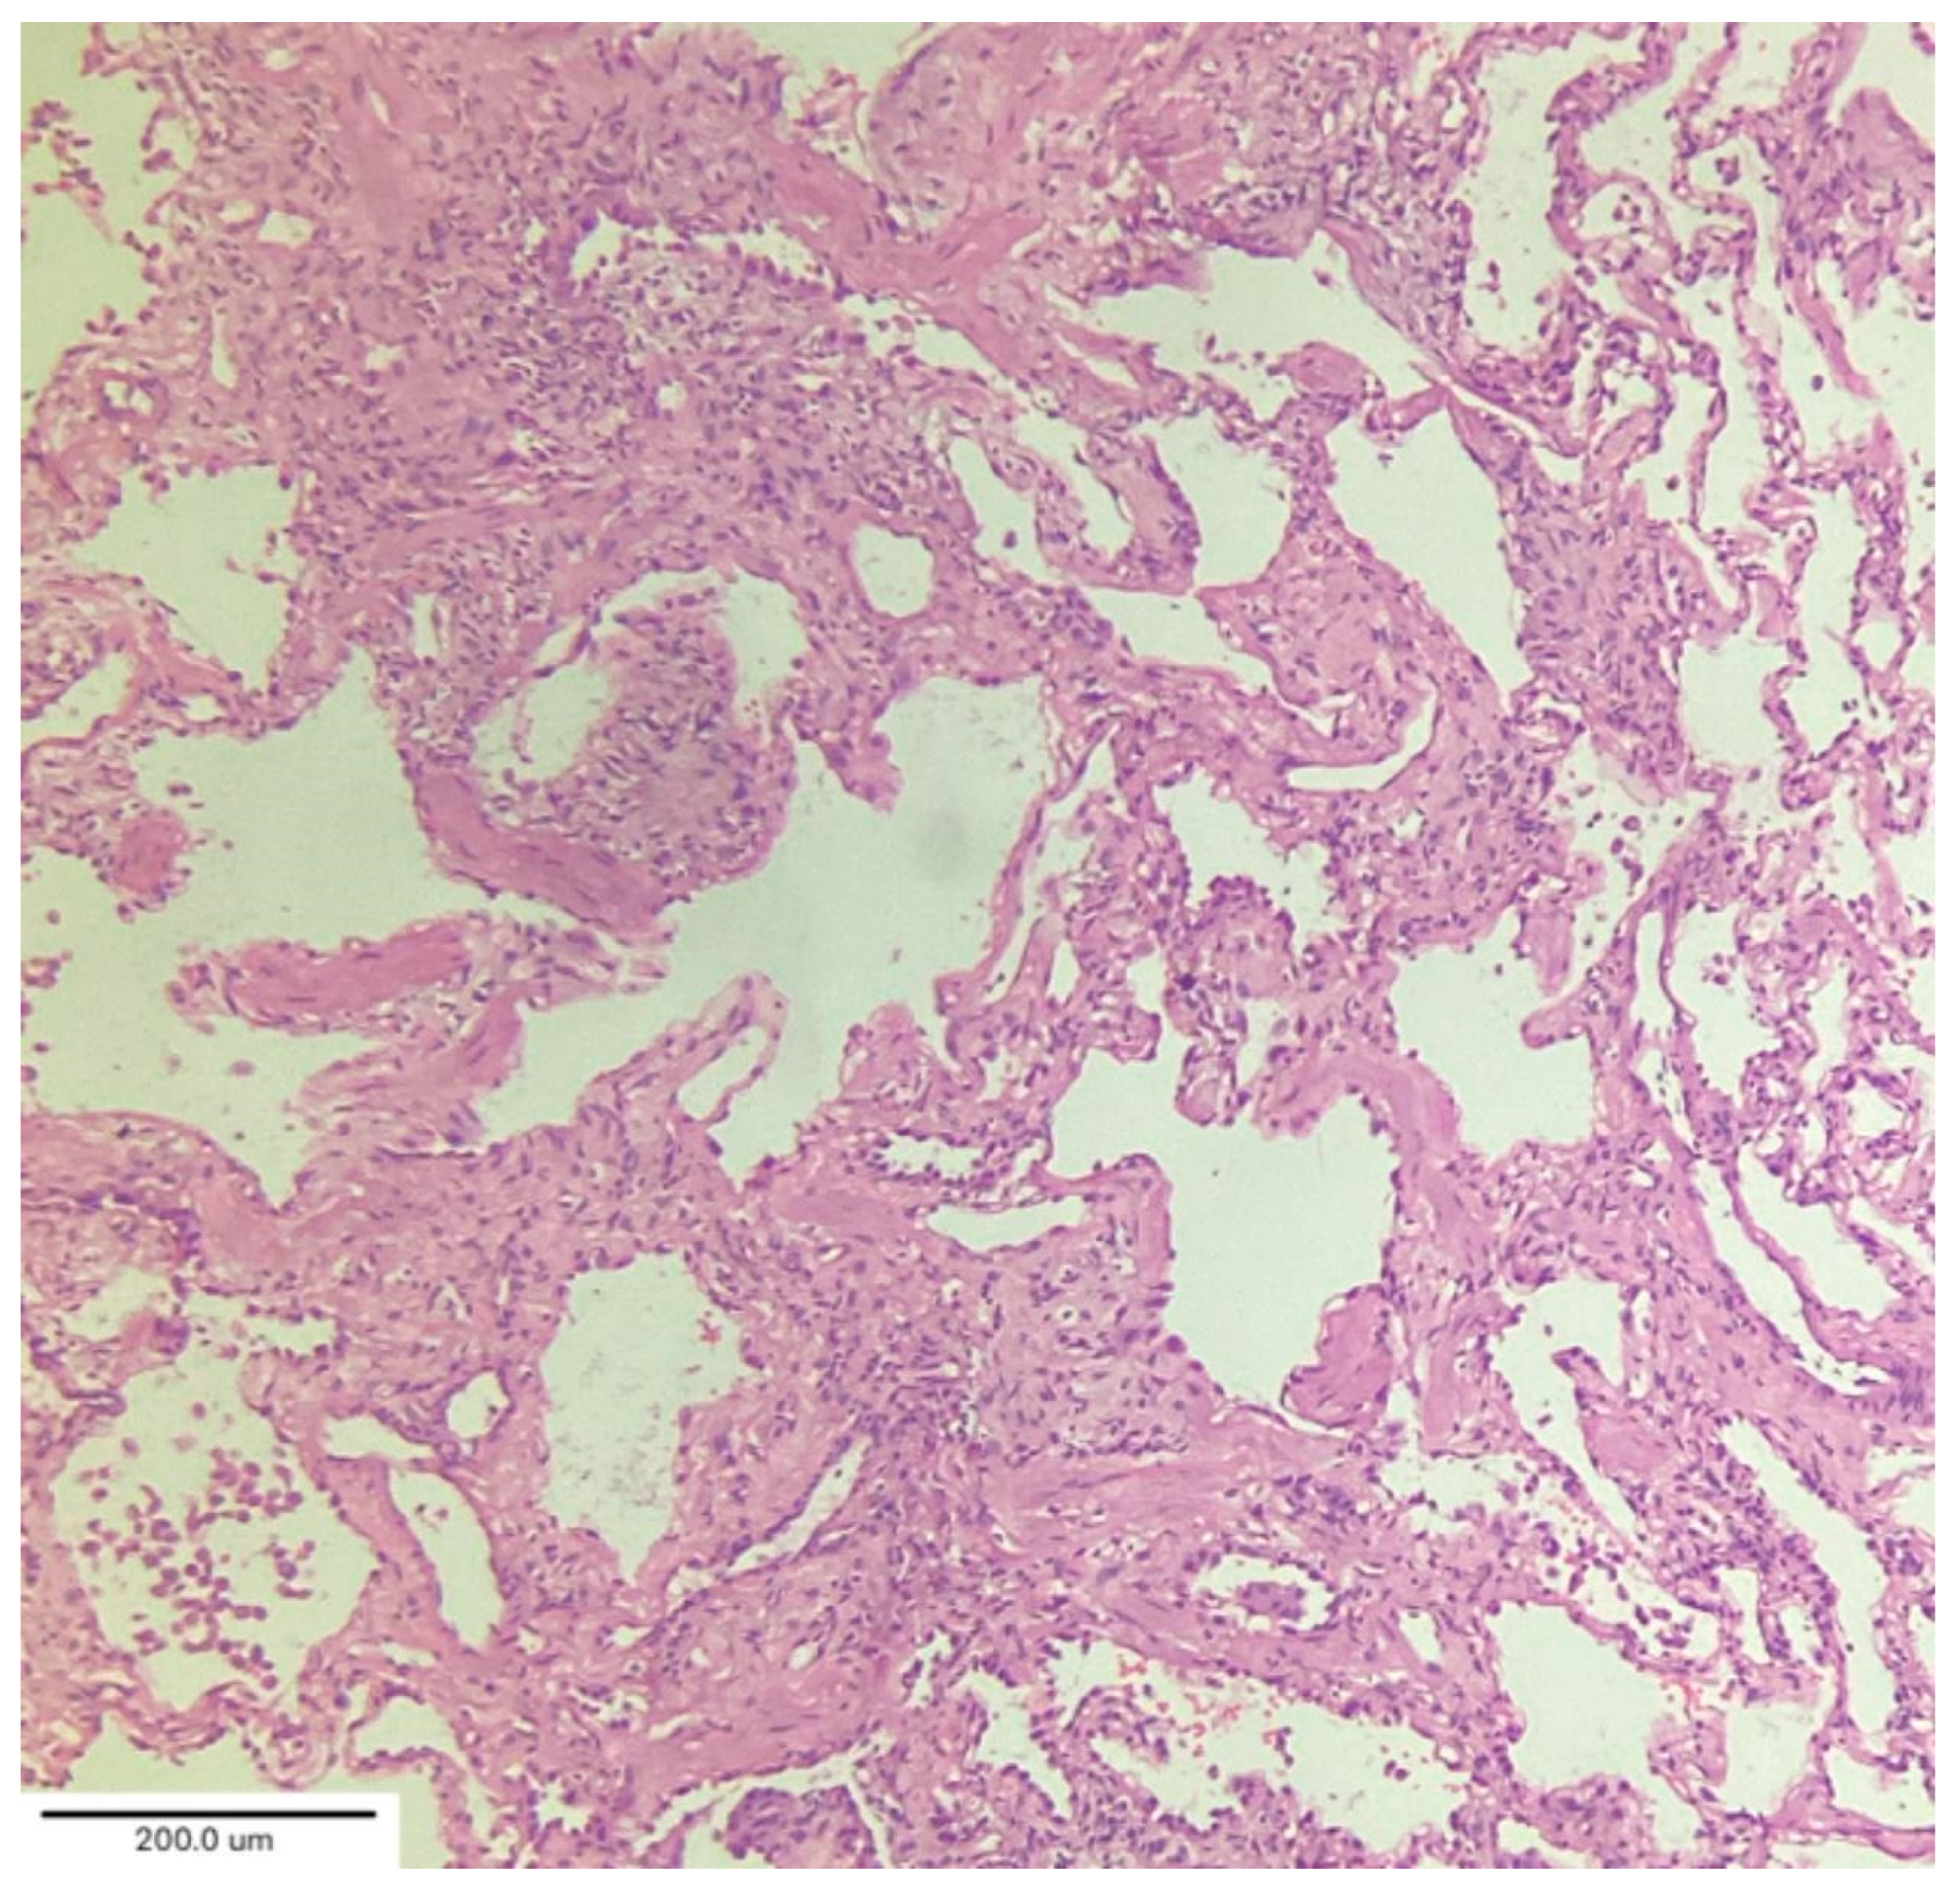

Cluster 2 (“acute/subacute injury”) was characterized by a great variety of lung injury patterns, including diffuse alveolar damage, organizing pneumonia, and fibrosing nonspecific interstitial pneumonia. The histopathology included diffuse thickening of the alveolar interstitium by myofibroblast proliferation and dense fibrosis. Remnant alveolar spaces showed type II pneumocyte hyperplasia (Figure 5), which expressed phosphorylated signal transducer and activator of transcription 3 (pSTAT3) and Ki67. Nodular lymphocytic infiltrates were noted in the perivascular and interstitial spaces.

In their analysis of cryobiopsies in post-COVID-19 patients, Culebras et al. [34] described the following findings: OP with Masson bodies (Figure 6), varying degrees of lymphoplasmacytic interstitial infiltrates and interstitial giant cells, and patchy collagenous interstitial/alveolar scars in the absence of fibroblastic foci. The fibrosis was confined in shape and distribution to “old OP.” No clear irreversible fibrosis or any classic pattern (UIP or NSIP) or smoking-related interstitial fibrosis, was observed. There were no hyaline membranes, fibroblastic enlargement of the interstitium, or thrombi observed in these biopsies. The most common injury pattern encountered on histologic analysis of postmortem and explant biopsies after COVID-19 is diffuse alveolar damage (DAD), the histologic correlate of ARDS. ARDS, both of infectious and non-infectious origin, may progress to the development of significant and irreversible pulmonary fibrosis [35].

A case series by Aesif et al. [35] described the presence of diffuse interstitial fibrosis vaguely resembling an NSIP pattern (Figure 7) and areas of microscopic honeycombing in patients after a 4-month follow-up period. Fibroblastic foci were not observed in the biopsies. Incorporating biopsy findings into the post-COVID-19 multidisciplinary evaluation can help to identify key patient subgroups, understand the pathogenic mechanisms of ILD progression, and create better patient-specific treatment protocols that improve clinical outcomes. [36,37]

TBLC procedure is reported in Figure 8.

Figure 5. Hyperplastic alveolar epithelial type II cells (AECII). Magnification: H&E ×100.

Figure 6. Organizing pneumonia with Masson bodies (arrow) and varying degrees of lymphoplasmacytic interstitial infiltrate. Magnification: H&E ×40.

Figure 7. Diffuse interstitial fibrosis with nonspecific interstitial pneumonia pattern. Magnification: H&E ×100.

Figure 8. Endobronchial cryobiopsy procedure (A) supported by radiological imaging (B) of the right inferior lobe. Courtesy of Pallav L. Shah.